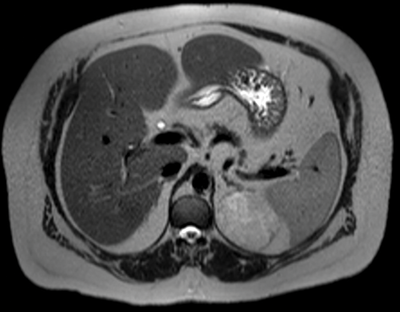

where E is the HU on the early post-IV contrast scan, D is the delayed scan and U is the unenhanced scan. A cut-off of >60% has been shown to diagnose a benign adenoma with a sensitivity of 88% and a specificity of 96% [5] (Figure 3).

Figure 3:

Top: Unenhanced CT (HU 23).

Centre: Arterial phase CT (HU 74).

Bottom: Delayed phase CT (HU 37).

Absolute washout = (74-37)/(74-23)x100 = 37/51x100 = 72.5% in keeping with adenoma.